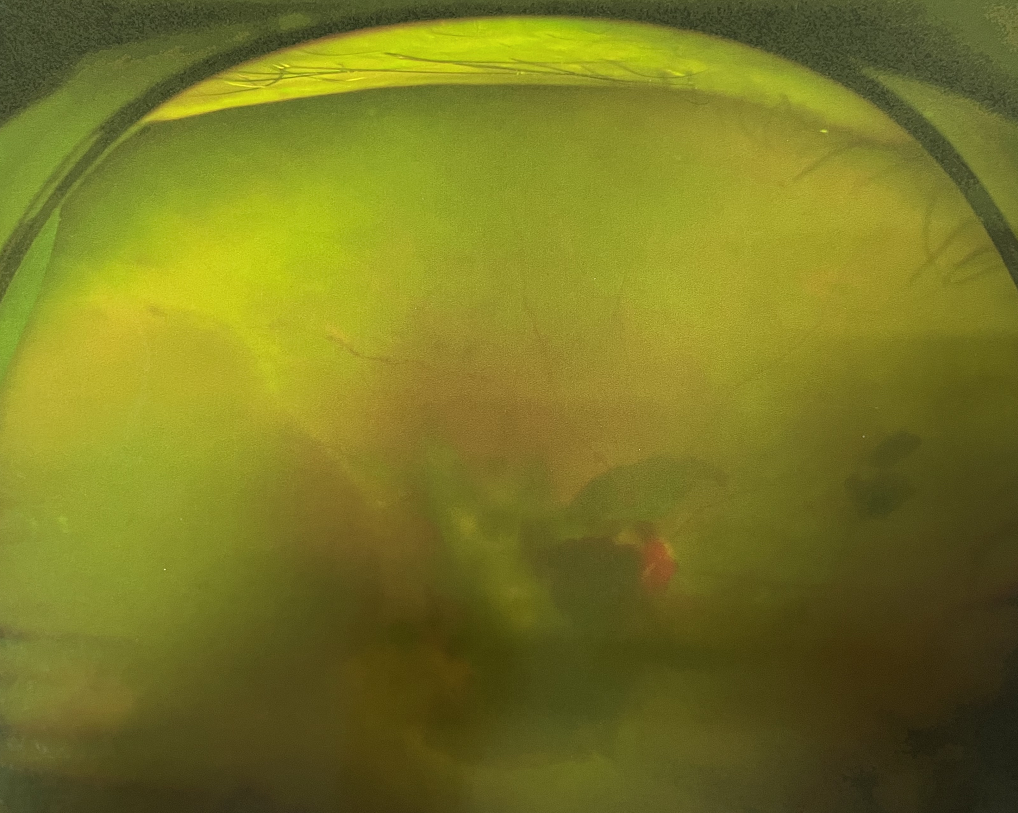

眼底出血是指眼內視網膜出血,或玻璃體內出血。眼底位于眼睛深處,所以這類出血只靠肉眼是看不到的,早期可能不紅、不痛、不癢,需通過專業(yè)的眼底檢查才可看到,往往短期內就可造成視力驟降甚至失明!

同樣的,眼底出血也是一種癥狀,而非病種。誘發(fā)眼底出血的原因很多,常見的有全身性血管病和血液病、視網膜血管異常、機械性阻塞、炎癥性疾病或免疫復合物侵犯血管壁等。

眼底出血是較為嚴重的眼疾,治療不及時會有失明的風險。一旦眼睛出現(xiàn)視力下降、視物變形、視野缺損或眼前有黑影等視覺異常的情況,應及時到醫(yī)院進行眼底檢查,早發(fā)現(xiàn)、早治療,以免貽誤病情。